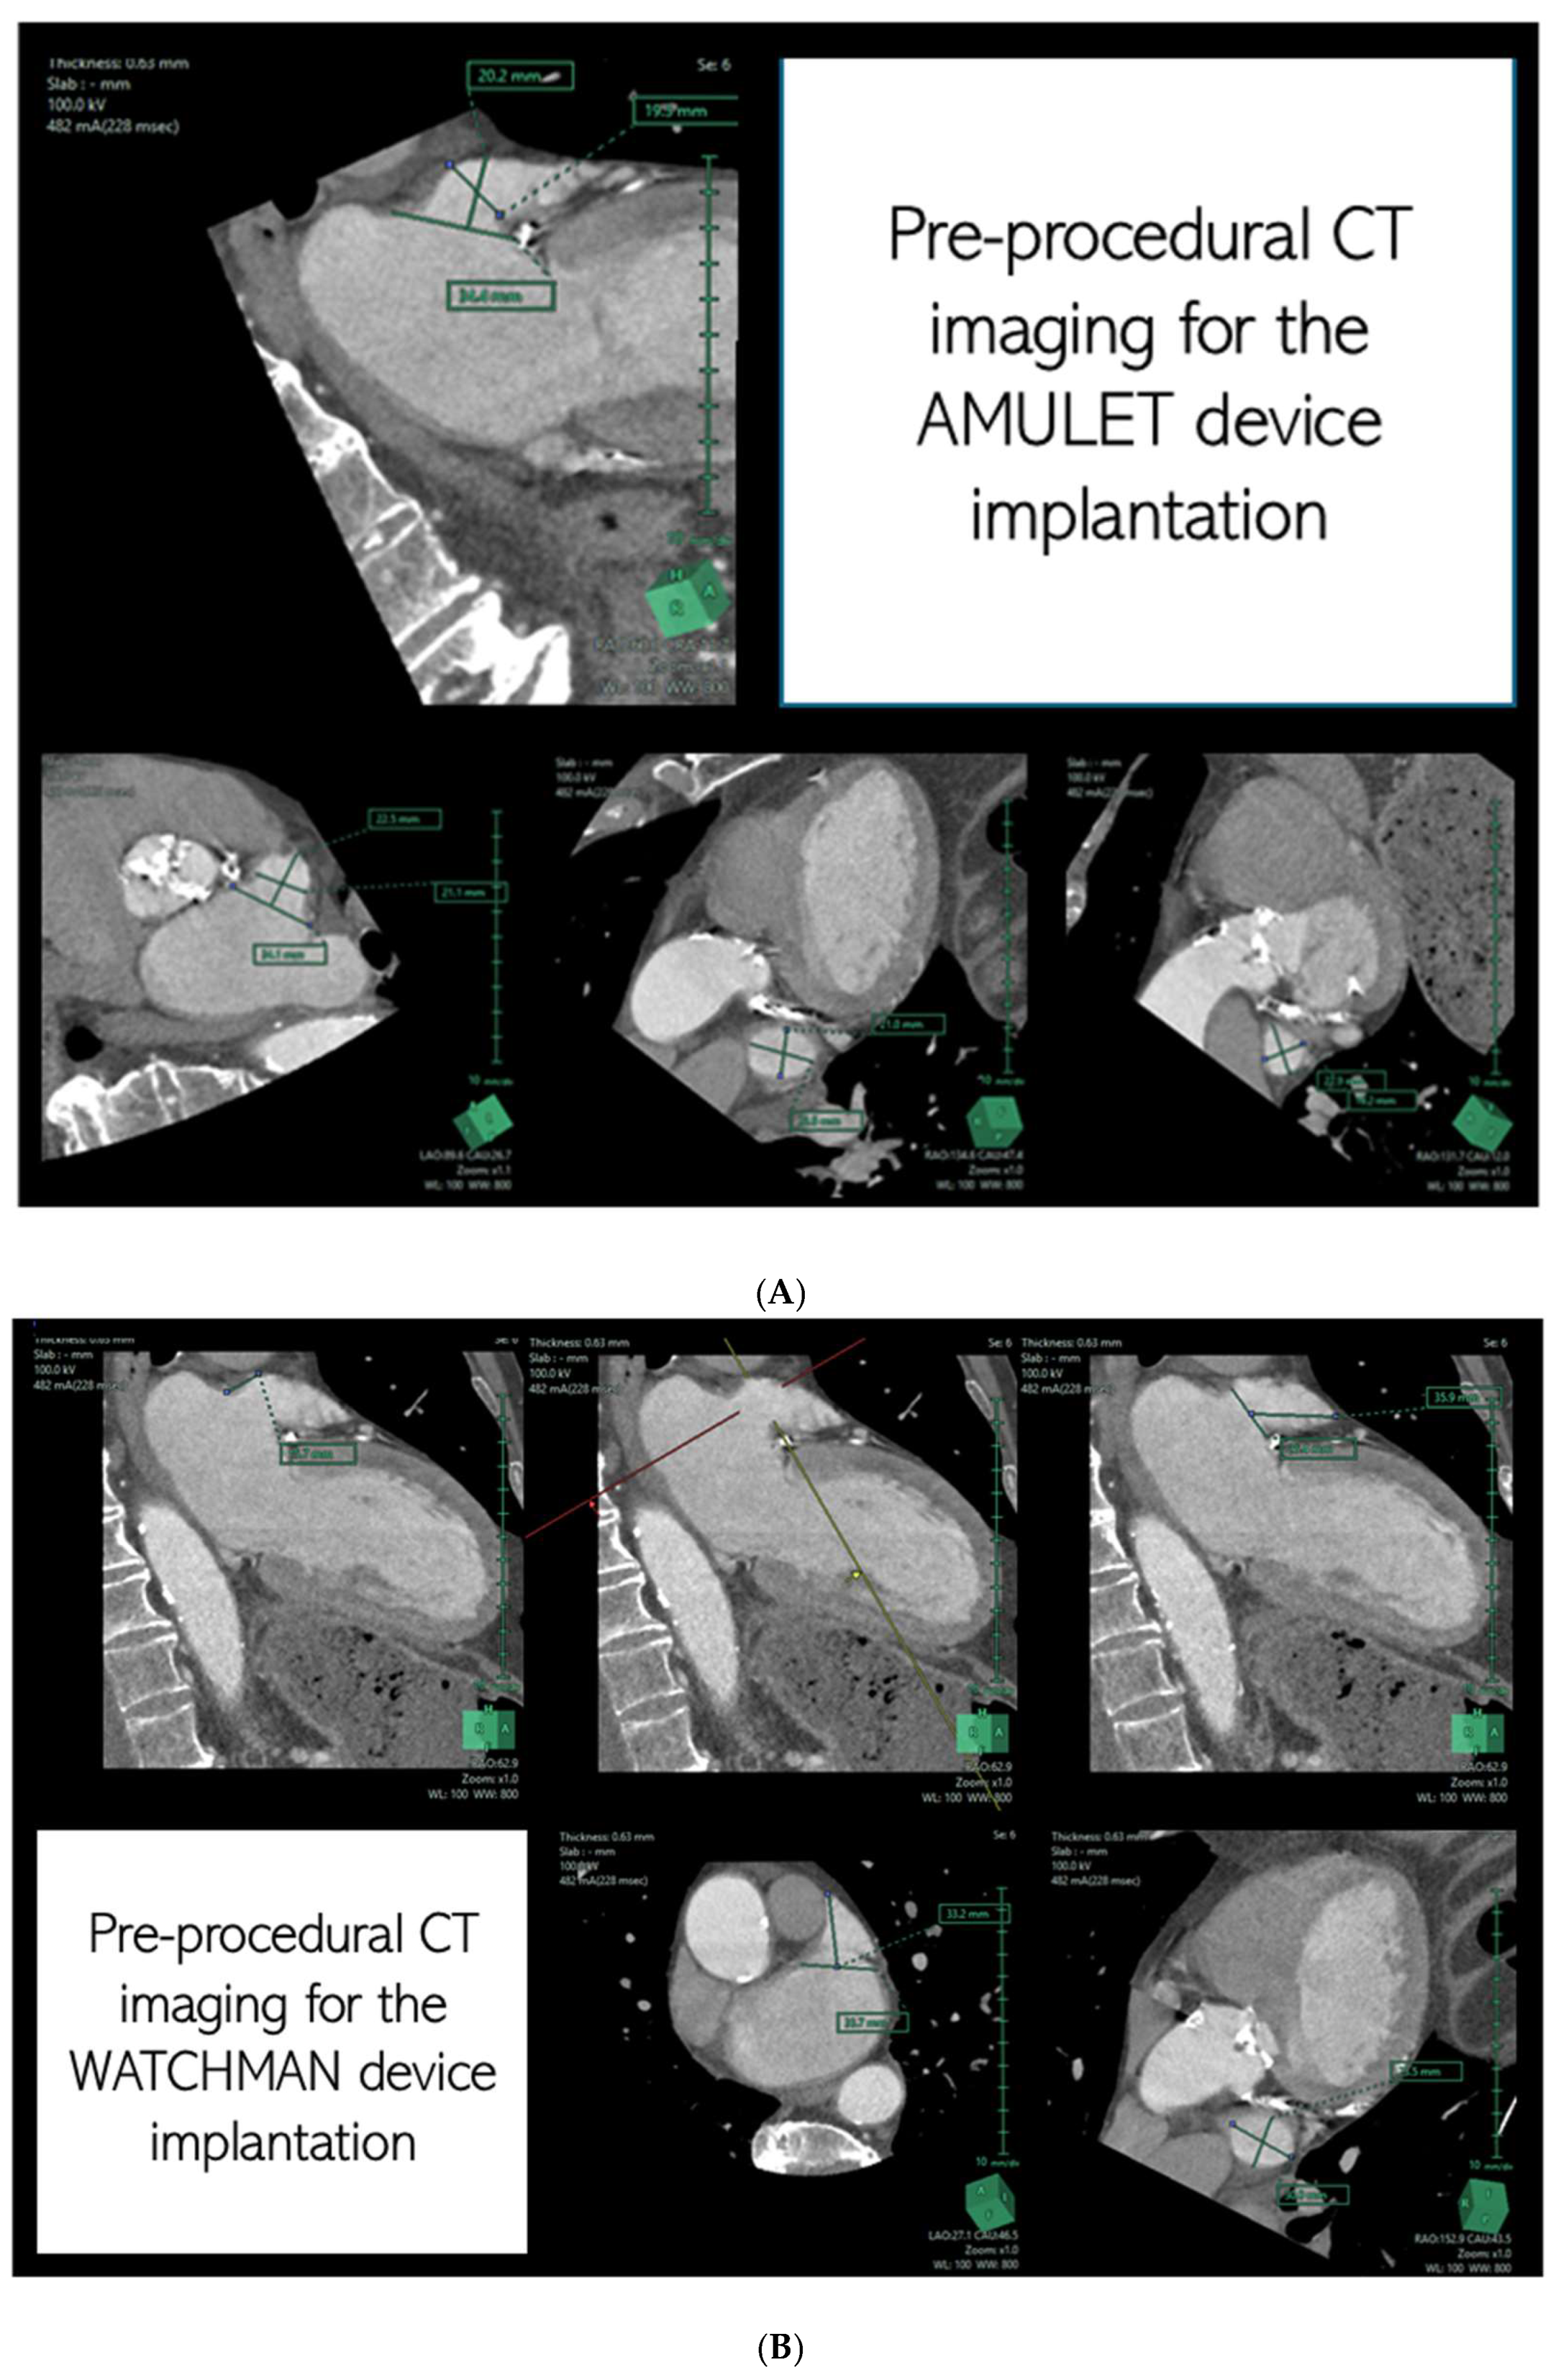

- By providing detailed anatomical assessment, including LAA dimensions, peak emptying velocity, and surrounding structures.

- By determining optimal fluoroscopic angles and guiding transseptal puncture locations for accurate device delivery.